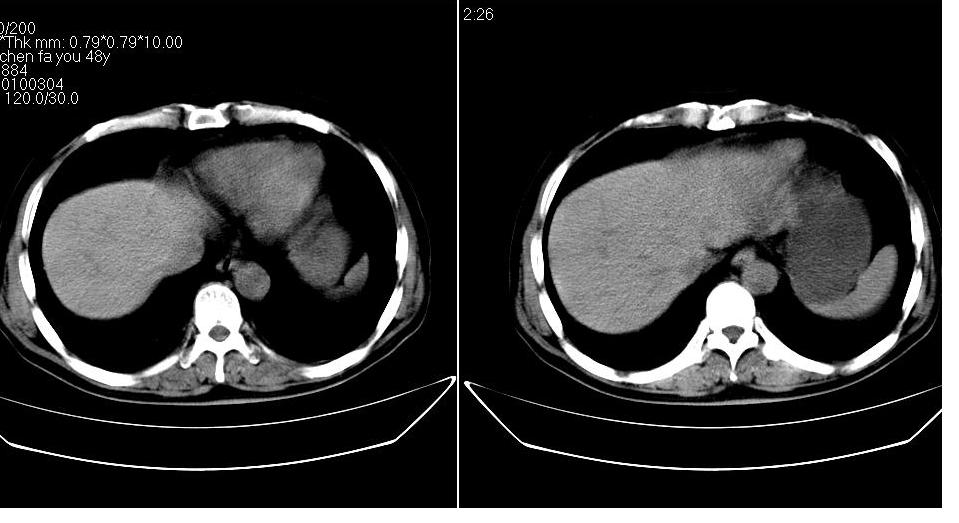

男 48岁,09年8月份在上级医院确诊胰头癌,准备在我院化疗。

胰头体积增大内见低密度影考虑为占位,肿瘤性病变可能性大。

胰头体积增大,外形不规则,密度欠均,支持胰头癌可能性大。